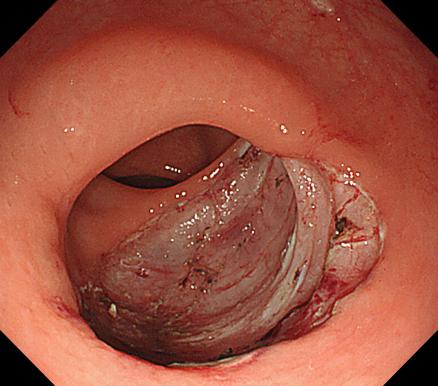

c617422923344d8ab1fe329c78d7814e.Jpeg5755b6aa8ded4797a794f5f01a4f88e6.Jpeg

食管靜脈曲張             內(nèi)鏡下套扎術(shù)

食管靜脈曲張?zhí)自g(shù)(EVL):治療食管靜脈曲張、胃底靜脈曲張破裂出血、藥物止血無(wú)效者;既往有食管靜脈曲張破裂出血史者預(yù)防再出血。